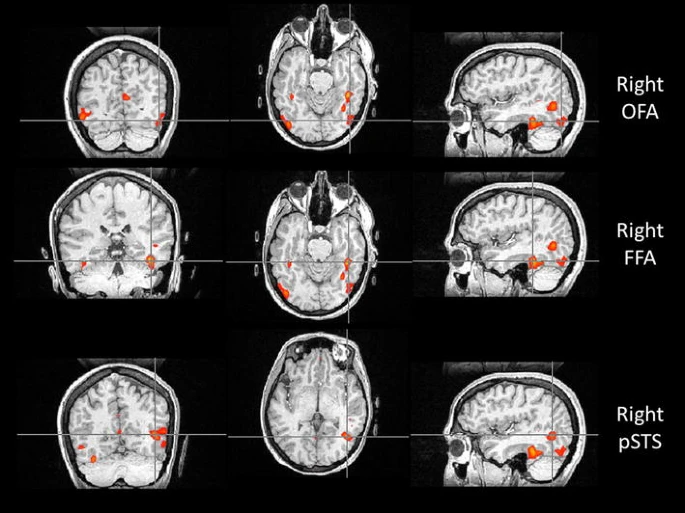

比如,位于枕叶的枕叶面孔区(Occipital Face Area, OFA)就像识脸网络的“先锋部队”。它专门处理眼睛、鼻子和嘴巴等五官“零部件”。当一张脸出现在我们眼前时,OFA 只需 约 100 毫秒 就能被激活,迅速对局部特征进行拆解,并将信息传递给 FFA 和上颞沟(Superior Temporal Sulcus, STS)。所以如果 OFA 出现问题,识别人脸就会变的很困难。

如果说 OFA 的作用是拆解五官,那么 STS 则更像是一个“动态解码器”。它对静态的面孔特征兴趣不大,却对动态特征极为敏感,尤其擅长捕捉 一颦一笑、眼神转动、嘴唇开合等细微变化。

正因为有 STS 的参与,我们不仅能认出“这是谁”,还能理解“他在表达什么情绪”“注意力投向哪里”,甚至在一定程度上推测对方的意图。STS 的参与也解释了为什么比起静态照片,在现实生活或视频中,我们更容易认出熟人。

与认脸有关的三个核心脑区,自上而下依次为:OFA(枕叶面孔区)、FFA(梭状回面孔区),以及 STS(上颞沟)。